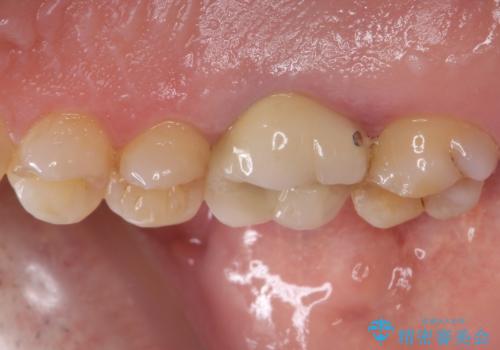

虫歯が歯肉の奥深くにまで及んでおり、歯肉が腫れやすい状態となっていたため、歯肉の切除並びに歯槽骨の形態修正を行い、虫歯が歯肉の外に出てくるようにした上で、オールセラミックにて補綴することとしました。

歯間ブラシを通す度に出血をするのは、ご自身の磨き方が悪いからと思っていらっしゃいましたが、治療後は全く出血することがなくなり、患者様には大変満足していただきました。